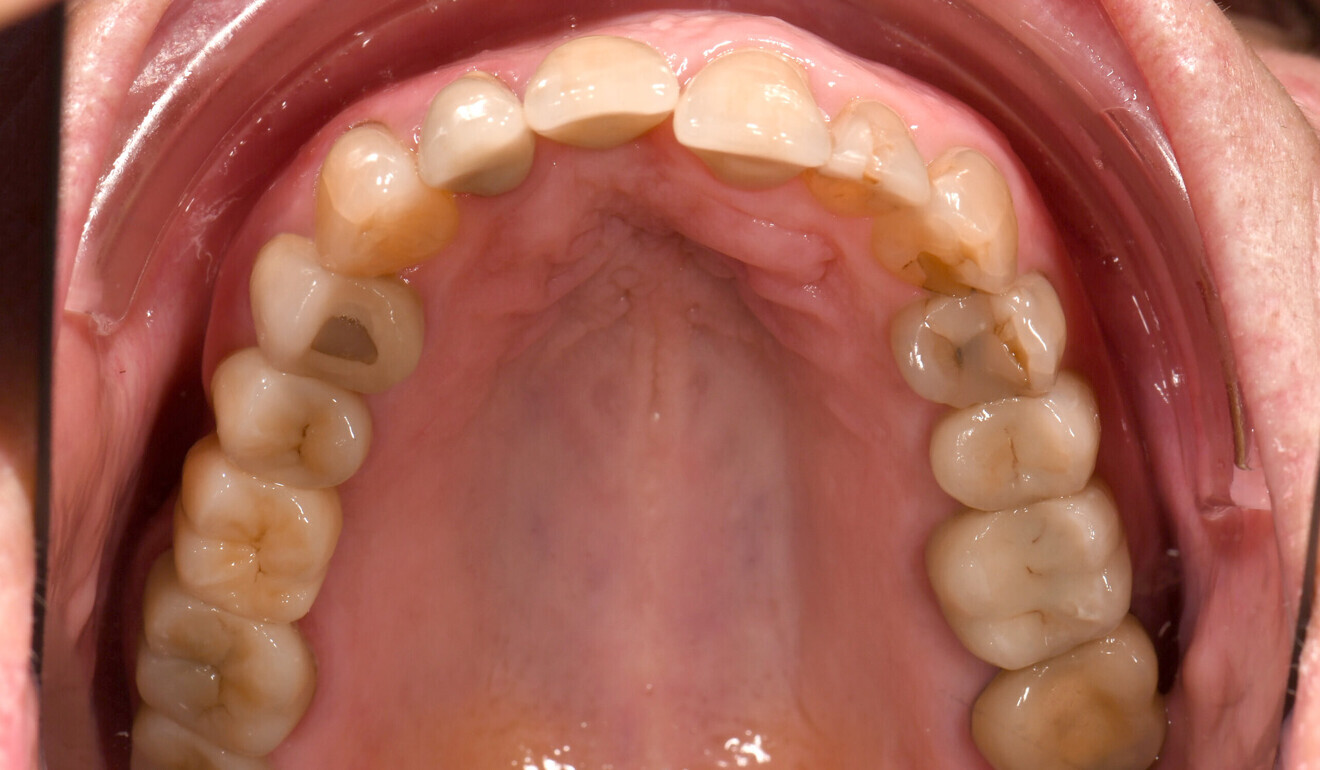

Fig. 3: Initial situation, occlusal view of the mandible.